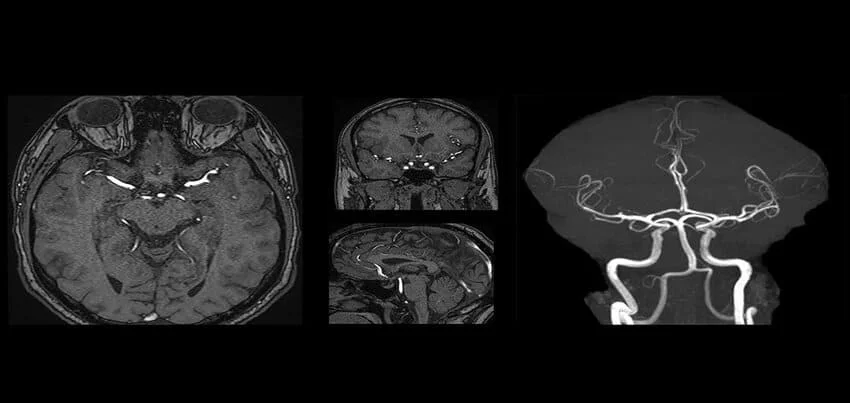

A Brain MRI, also known as an MRI Brain Scan, utilizes Magnetic Resonance Imaging of the Brain to provide detailed images of brain structures. For a comprehensive evaluation, a Brain Angiography can be performed alongside the MRI. This combined MRI Angiography Brain procedure, often referred to as an MRI Brain with Angiogram, visualizes the blood vessels within the brain, aiding in the diagnosis of vascular conditions. The MRI Brain Angiography Procedure involves the injection of a contrast agent to enhance the visibility of blood vessels, making it a crucial step in the Brain Angiography Procedure. The cost of an MRI Angiography Brain varies depending on the healthcare facility, but it is generally considered a valuable investment for accurate diagnosis. The Brain Angiography Interpretation provides insights into abnormalities such as aneurysms or blockages. An MRI Brain Test, when combined with Angiography, becomes an Angiography Brain Test, offering a dual advantage of structural and vascular assessment. The Angiography MRI Brain technique is pivotal in identifying and treating brain disorders. For those wondering, “What Is A Brain Angiography MRI?” it is a specialized imaging technique combining Brain MRI with Angio, essential for a thorough evaluation. Understanding the Brain Angiography Cost and MRI Brain with Angio benefits helps in making informed healthcare decisions.

Magnetic Resonance Imaging (MRI) Brain + Angiography is a medical imaging test that uses a strong magnetic field and radio waves to create detailed images of the brain and its blood vessels. This non-invasive procedure allows doctors to detect abnormalities or injuries in the brain and the blood vessels that supply it.

The interpretation of MRI Brain + Angiography images requires specialized training and experience. The radiologist will examine the images and prepare a report for the patient’s doctor. The report may indicate the presence of any abnormalities or injuries in the brain or blood vessels, the size and location of any tumors, and the extent of any blockages or abnormalities in the blood vessels.